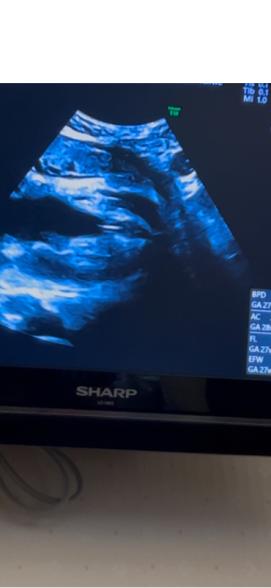

エコーのお写真をありがとうございます。

拝見いたしました。

女の子のように見えますが、はっきりとしたお返事が難しくなります。